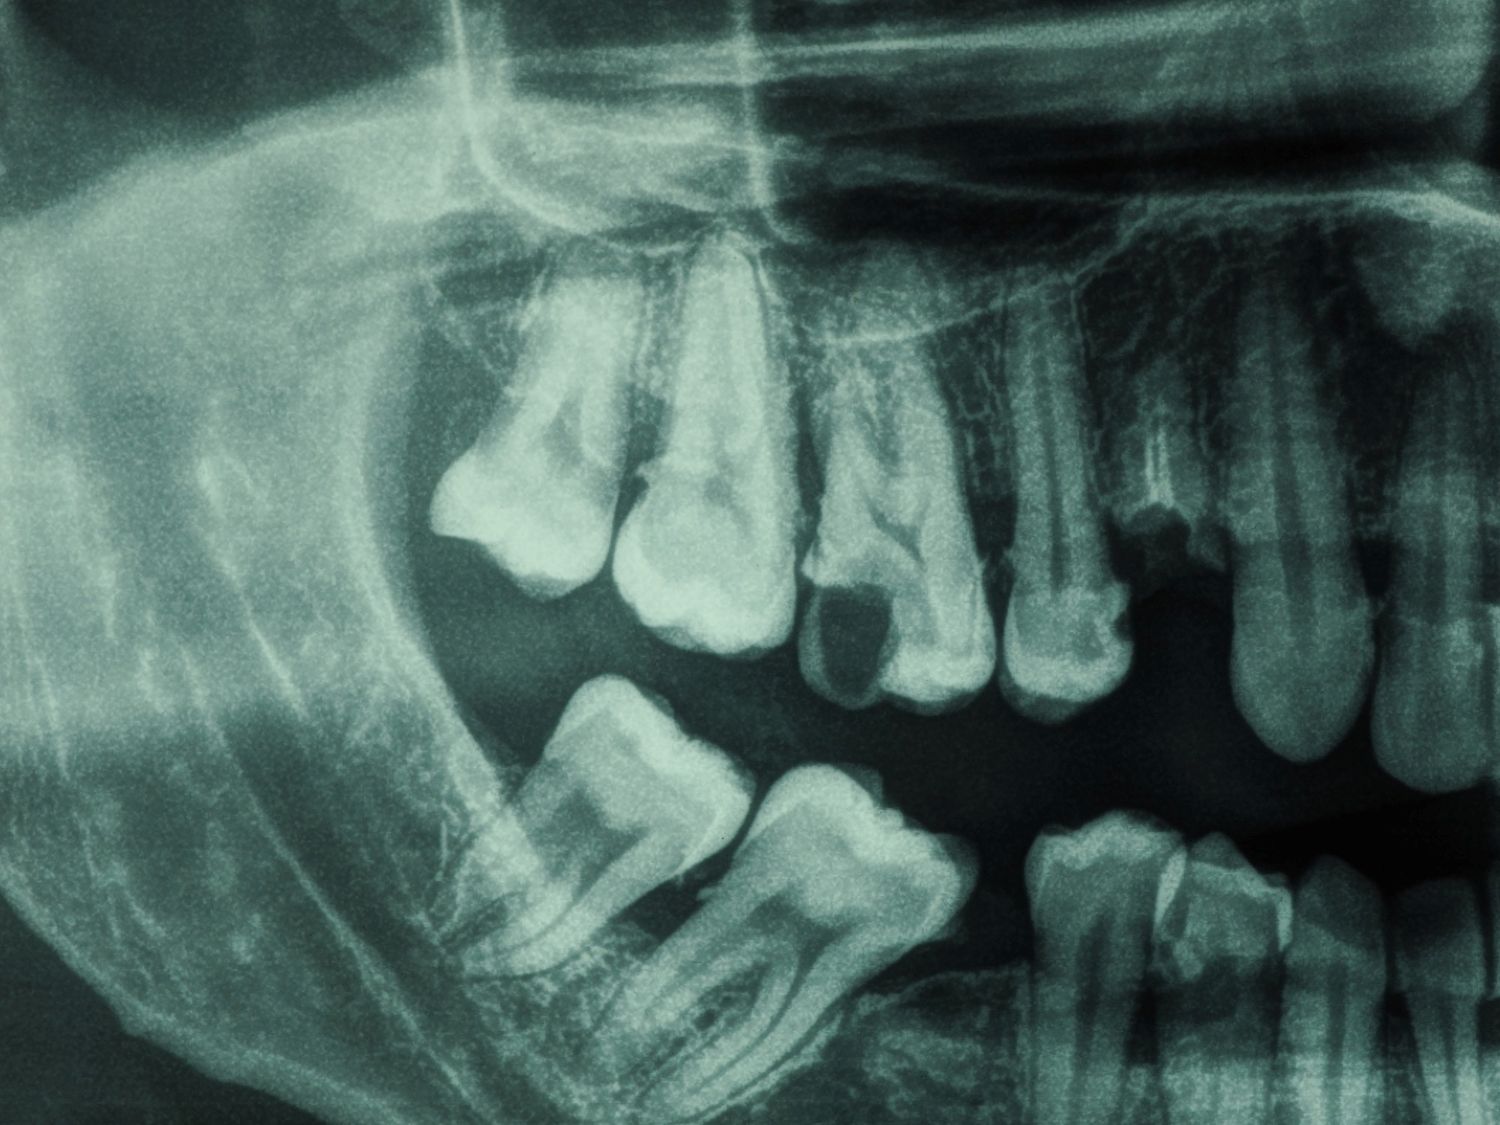

Sometimes the problem goes deeper than what we can see. When bacteria reach the inner nerve of the tooth, it can cause persistent pain or infection.

A root canal treatment (RCT) aims to remove the infection, relieves your pain, and saves your teeth.

For: Compromised pulp (decay or cracked tooth)

We strive for single visit whenever possible